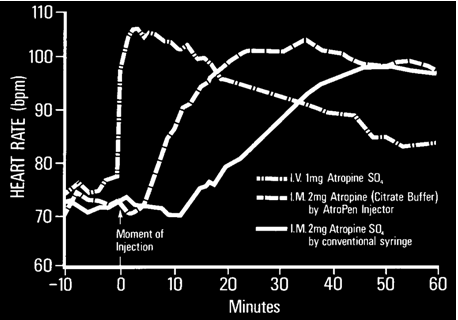

Atropine: Route of Administration |

In approximate order of preference, the following routes of administration can be used for the administration of atropine

AdultsThe most commonly recommended initial doses range from 2 to 6 mg (0.02-0.04 mg/kg). (du Toit, Muller et al. 1981) Authors differ with regards to how frequently these doses should be titrated. Recommended dose intervals vary widely from every 2 to every 30 minutes (Willems 1981; Goswamy, Chaudhuri et al. 1994; Singh, Batra et al. 1995; Carlton, Simpson et al. 1998; Schenker, Louie et al. 1998; Tareg et al. 2001; Erdman 2004; Fernández 2004) (or 1-3 2 mg autoinjector doses). (Sidell 1997) After adequate control of secretions, Du Toit et al. started their patients with an I.V. maintenance drip of 0.02-0.08 mg/kg/hr titrated to effect. (du Toit, Muller et al. 1981) One reported case required 0.5-2.4 mg/kg/hr, I.V. drip, during 5-weeks of treatment. (LeBlanc, Bensen et al. 1986) Some attempts have been made (mostly for nerve agents) to characterize the doses needed according to severity of symptoms. (See the table below for an example.) The goal of therapy with atropine is to reverse life-threatening signs and symptoms (i.e., respiratory distress), and make the patient more comfortable. Currently it is thought that this does not necessarily require the reversal of all effects of the cholinesterase inhibitor [e.g., miosis (pupillary constriction)]. Generally, in patients with severe symptoms, it is better to give too much atropine than too little. (Sidell 1997) Children under 12 years of ageMost authors' recommended doses range from 0.05-0.1 mg/kg boluses q 2-30 min. (Zwiener and Ginsburg 1988; Carlton, Simpson et al. 1998; Reigart and Roberts 1999; Fernández 2004) Pediatric atropine autoinjectors (0.5 mg, 1 mg sizes) (Food and Drug Administration 2003) See the chart below. Intravenous dripRecommendations for I.V. maintenance doses have ranged from 0.2-2.0 mg/hour (0.025 mg/kg/hr in children). (du Toit, Muller et al. 1981; Erdman 2004) OphthalmicTopical mydriatics, such as atropine, and homatropine, can provide relief from eye pain and reflex nausea and vomiting. However, these drugs cause blurring of vision, and should be reserved for cases with severe eye pain. (Sidell 1997) Warning: Hydrocarbons may be used as diluents in liquid formulations of cholinesterase inhibitors. In cases of ingestion, aspiration pneumonitis with acute respiratory distress syndrome may add to the muscarinic respiratory effects of the poison, but is unresponsive to atropine. (Reigart and Roberts 1999) |